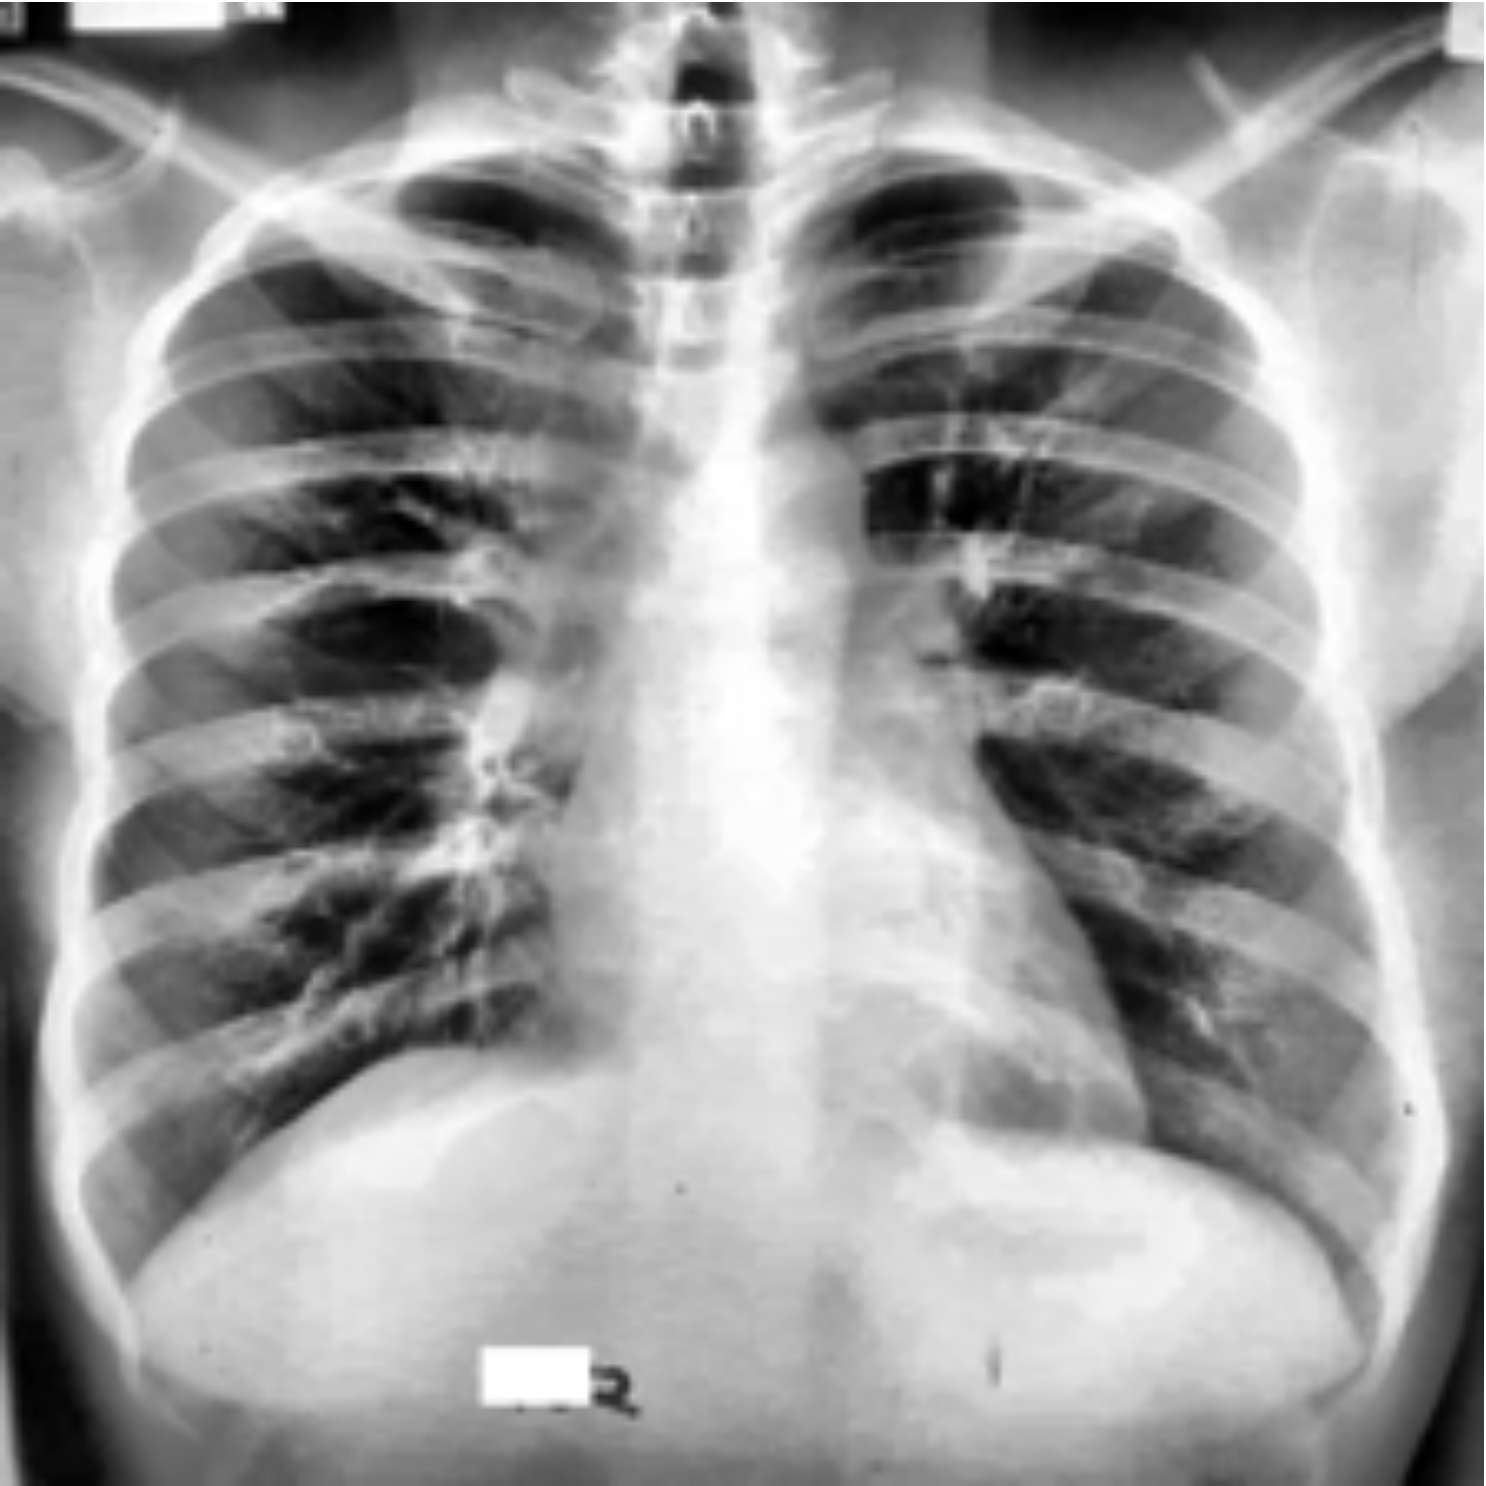

Figure 1: Images from the training dataset. (a) shows an image with active TB, (b) shows a TB negative image, (c) shows an image with latent TB, (d) shows an image with bounding box, and (e) shows an image with segmentation masks.